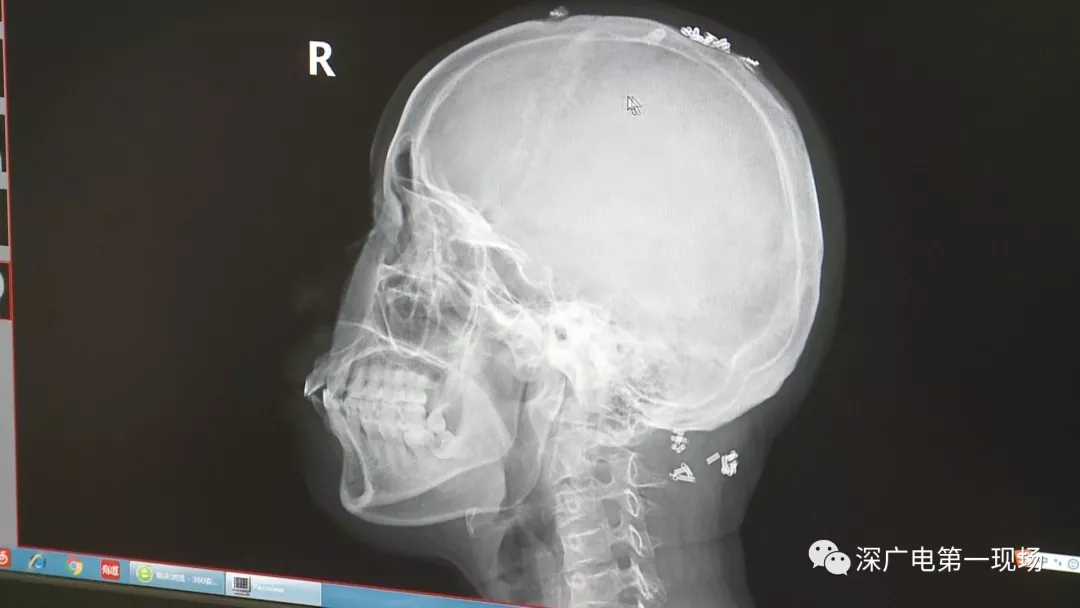

從X光影像圖片中可以看到

患者周身布滿了彈簧圈

深圳大學(xué)總醫(yī)院神經(jīng)外科副主任醫(yī)師陳富勇介紹,當(dāng)時檢查的時候發(fā)現(xiàn),該患者從頭部到腿部,基本上每個地方都有彈簧,很難數(shù)清具體數(shù)目。

陶主任表示,將這些彈簧圈取出也是一項大的工程,因為有的都已經(jīng)形成了包塊,所以想要取出還得先定位,再挨個手術(shù)取出,目前醫(yī)院方面已經(jīng)將患者頭部和頸部的部分取出。